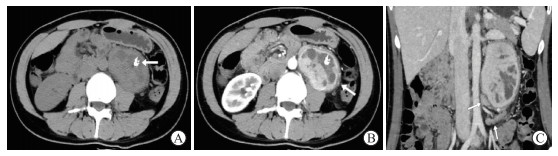

图  4   1例67岁男性腹部副神经节瘤患者的影像学表现(腹部阵发性疼痛4个月余,不伴高血压)

A:CT平扫示腹主动脉右侧见一类圆形实性肿块(箭头所示),CT值为47.2 HU;B:CT增强动脉期示肿块明显均匀强化,CT值为160.2 HU,瘤内及边缘可见血管影(箭头所示);C:冠状面CT增强静脉期示腹主动脉右旁肿块强化程度稍减低,CT值为117.5 HU,呈速升缓降强化模式,瘤周脂肪间隙清晰,未见肿大淋巴结. CT:计算机断层扫描.